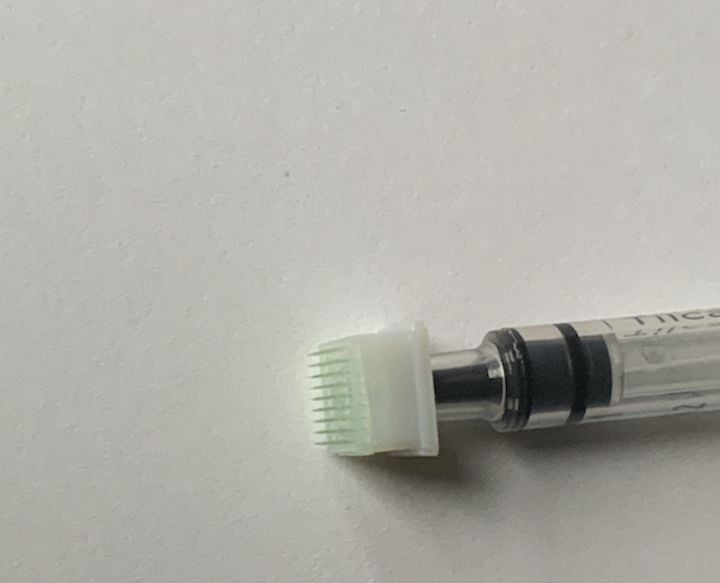

BMF Investigating Production Of 3D Printed Microneedles For COVID-19 Vaccines

BMF has been collaborating with Carnegie-Mellon University on a very promising approach to COVID-19 vaccines.